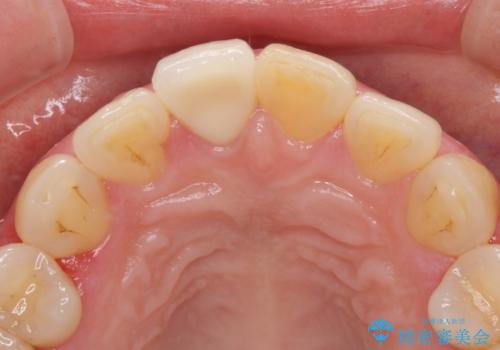

- 昔ぶつけて欠けた前歯をきれいにしたい、とご来院された患者様です。

プラスチックの詰め物が長年の劣化により変色していました。

オールセラミッククラウンの治療を行いました。

前歯2本のラミネート治療をご希望でしたが、前歯の見た目が悪いのは右上前歯1本が原因であり、左上前歯は虫歯などがなく、削るのはもったいないということをご説明しました。

また、右上の前歯は裏側までヒビが入っていることや、1層構造のラミネートよりも2層構造のオールセラミッククラウンの方が色の再現性も高いことから、右上前歯1本のクラウン治療をおすすめしました。